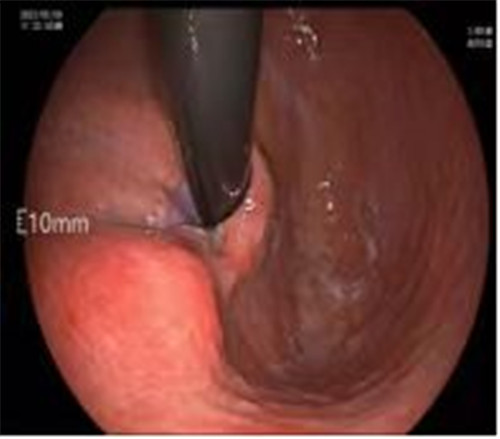

近期病例之一,圖片依次為:胃鏡、超聲胃鏡、ESE術(shù)中、術(shù)后、切下病變。

普通內(nèi)鏡是一種“直視”光學(xué)檢查,通過微型攝像頭將消化道管腔內(nèi)圖像實(shí)時(shí)清晰地呈現(xiàn)給檢查者;而超聲是一種“透視”的聲學(xué)檢查,通過人體組織不同的回聲特點(diǎn),對(duì)皮膚或粘膜以下的深部組織進(jìn)行觀察。超聲內(nèi)鏡則是兼兩者之所長(zhǎng),可以在直視的基礎(chǔ)上,了解表面以下的改變。

內(nèi)鏡超聲小探頭可用于探查消化道管壁腫物。消化道管壁分為4層,從內(nèi)到外依次為粘膜層、粘膜下層、肌層、漿膜層,不同分層內(nèi)的病變性質(zhì)各異。

內(nèi)鏡超聲小探頭可以判斷病變的起源、回聲性質(zhì)、生長(zhǎng)方式、大小等,從而協(xié)助醫(yī)生制定相應(yīng)的診療方案,也被稱作是普通內(nèi)鏡醫(yī)生的“透視眼”。